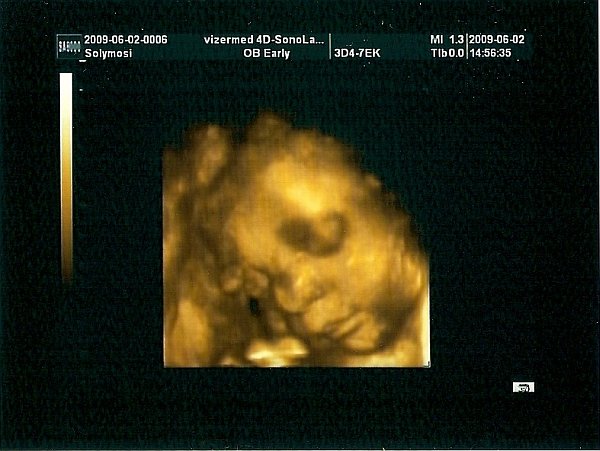

nagyon szép a pocid!